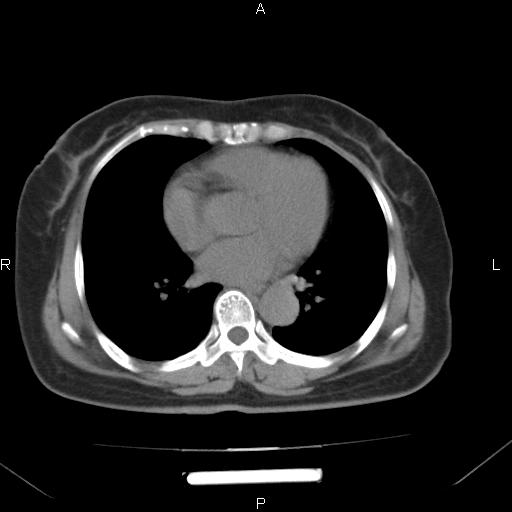

胸腺瘤

女、63Y 双眼睑下垂,早轻晚重。 胸腺瘤???

结果胸腺瘤